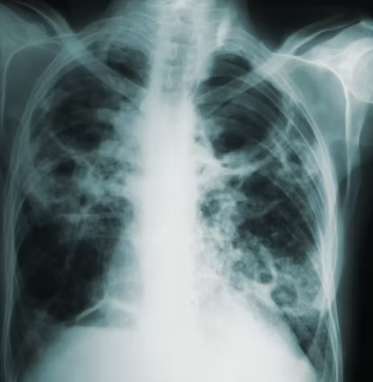

이 외에 흉부 X-ray 또는 CT를 통해 폐기종 변화나 다른 폐 질환 유무를 확인하고, 혈액 검사로 알파-1 항트립신 결핍증과 같은 특정 원인이나 합병증을 평가하기도 합니다. 의료진은 이러한 검사 결과를 종합하여 만성폐쇄성 폐질환의 진단과 중증도를 판단합니다.

만성폐쇄성 폐질환은 만성적인 경과를 보이는 질환이므로, 꾸준한 모니터링과 정기 검진이 매우 중요합니다. 주기적으로 폐기능 검사, 흉부 X-ray, 혈액 검사 등을 통해 폐 기능의 변화와 합병증 발생 여부를 확인해야 합니다.